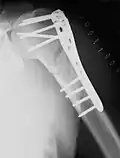

- Die winkelstabile Platte am proximalen Humerusschaft

-

Eine Fraktur am oberen Ende des Humerus -

Versorgung mit winkelstabiler Platte -

Ansicht in anderer Ebene